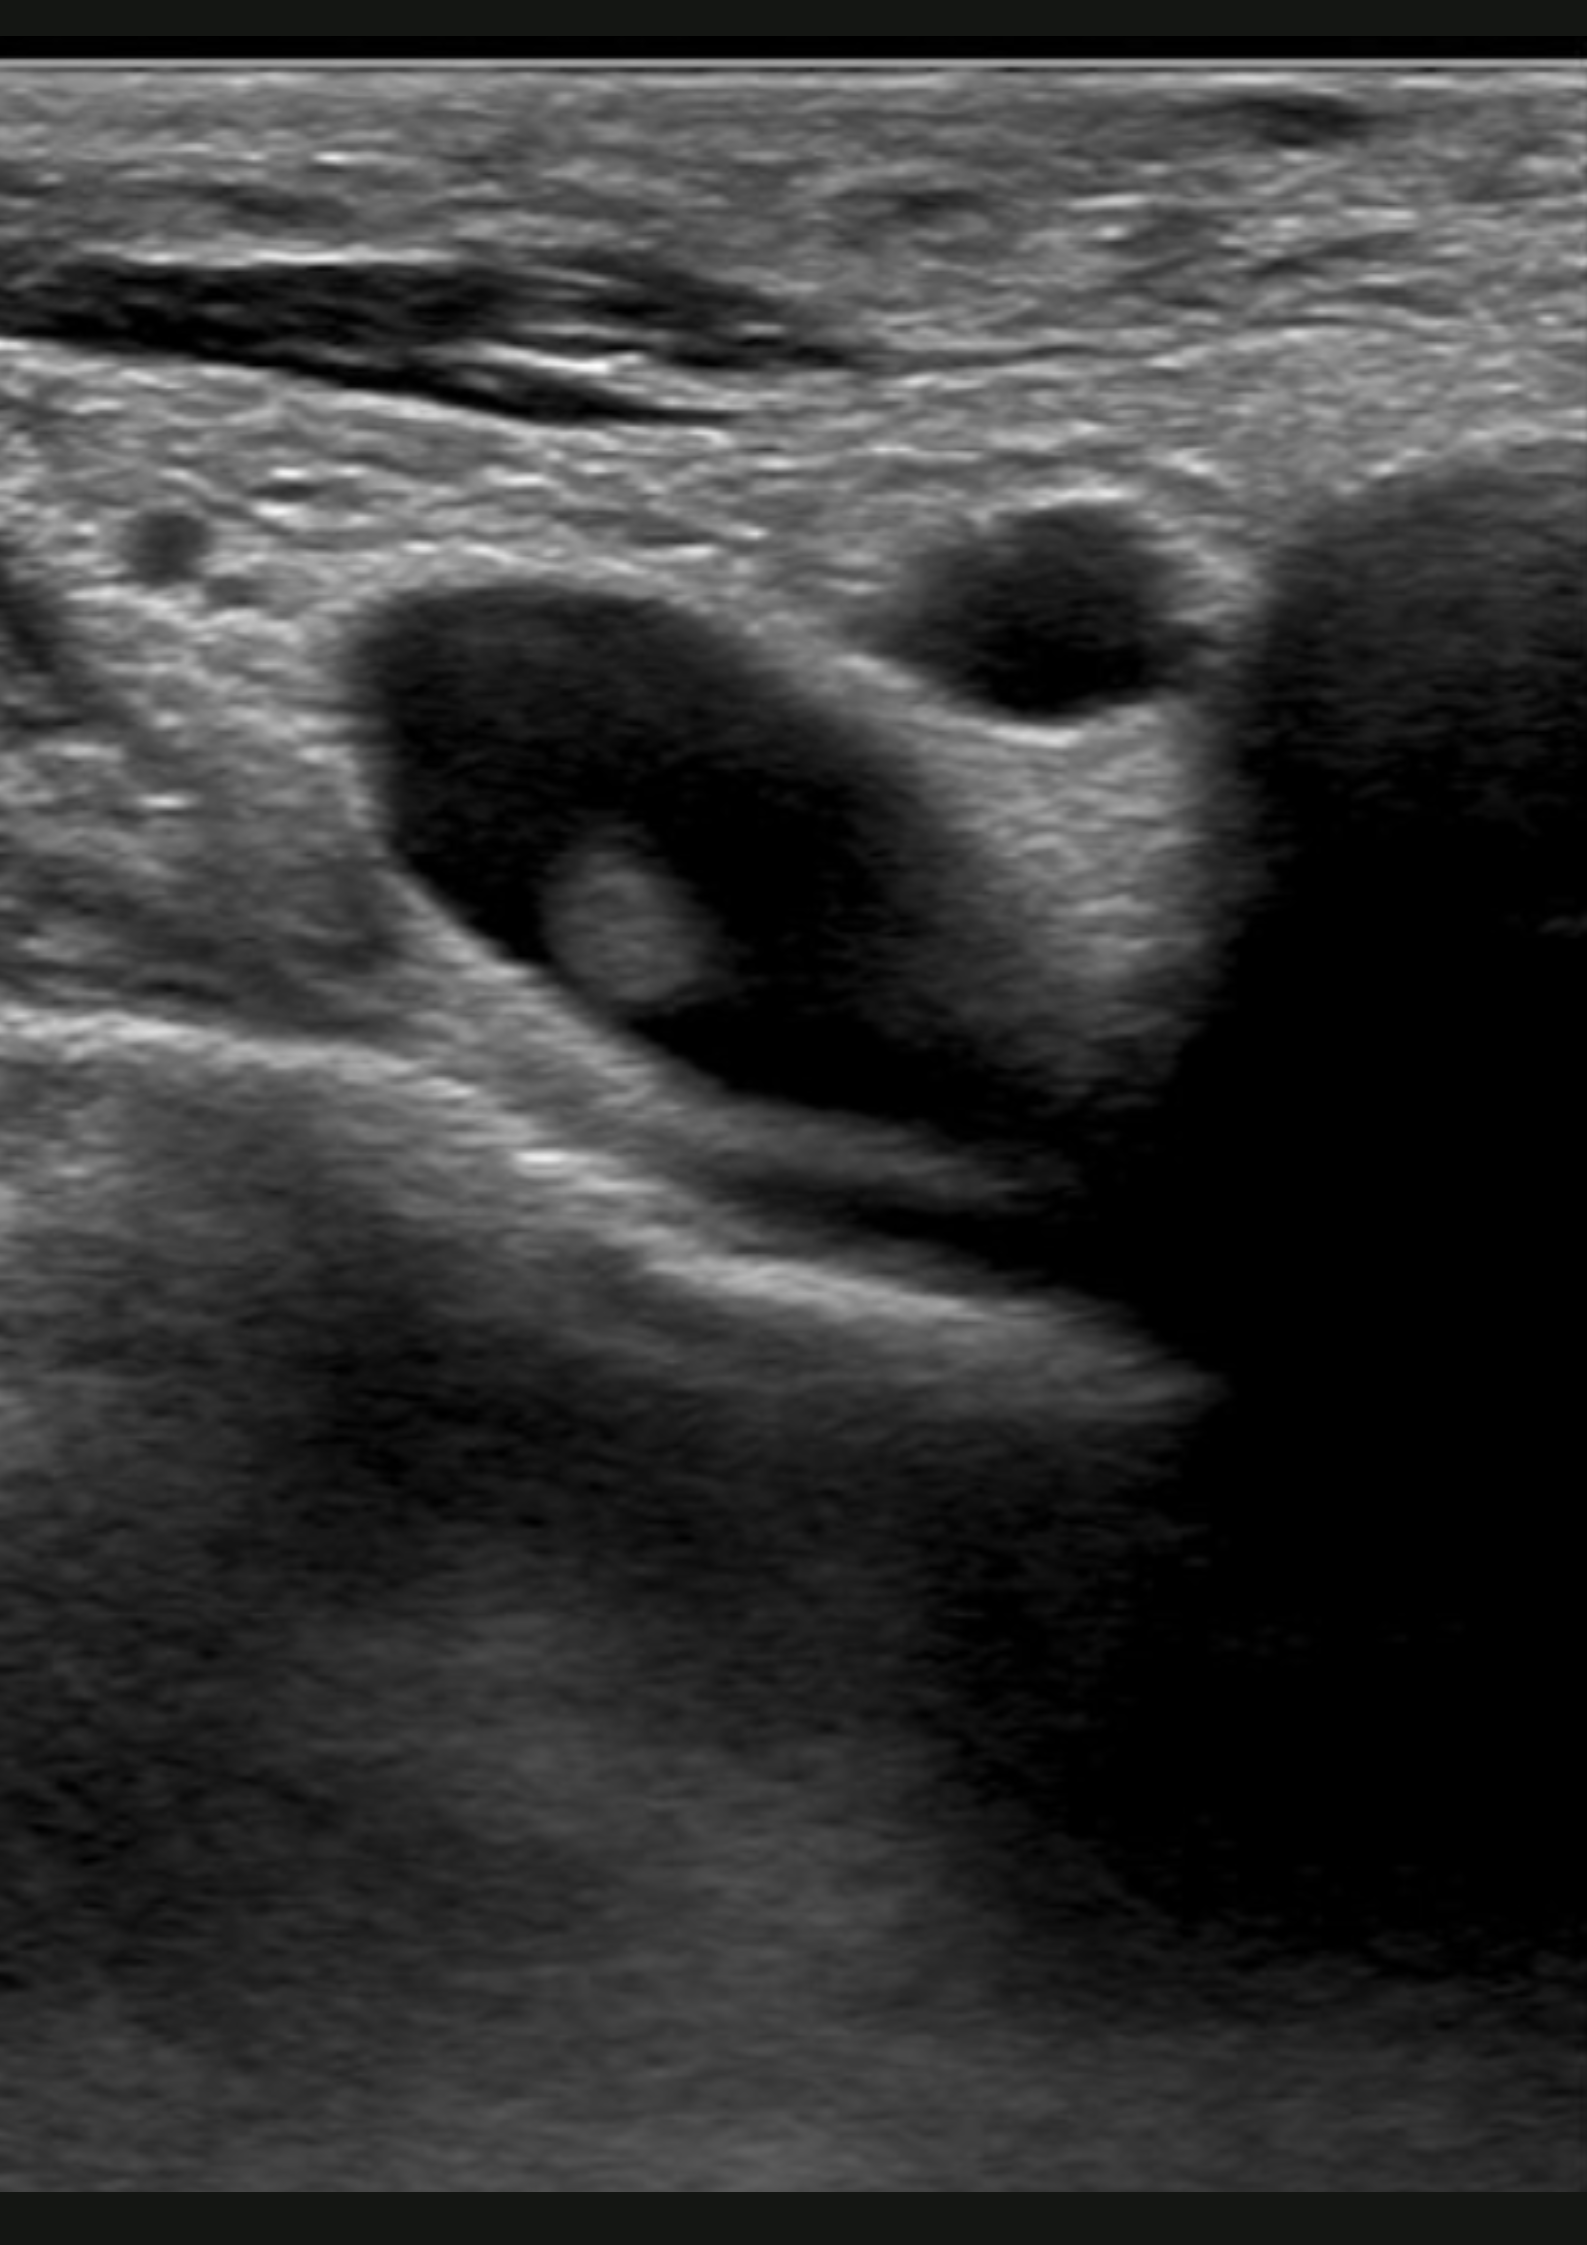

Hallazgos ecográficos

En la ecografía no apreciamos alteraciones musculares pero observamos dificultad para la compresión de la vena subclavia derecha en extensión.

Trombosis venosa profunda de sublcaiva, innominada, cefálica y yugular derecha.

Se remite a Urgencias del hospital de referencia con hallazgos de coagulación: INR 1.05, fibrinógeno 464, Dímero D 1222; y una ecografía de partes blandas que muestra una trombosis venosa de la vena subclavia derecha y vena innominada, con ligera extensión a la vena yugular derecha y cefálica derecha. Posteriormente, se inicia heparina subcutánea y se realiza fibrinolisis con perfusión de urokinasa. En el estudio de coagulación posterior se determinó una hiperhomocisteinemia y probable síndrome antifosfolípido (Paget-Schroetter).